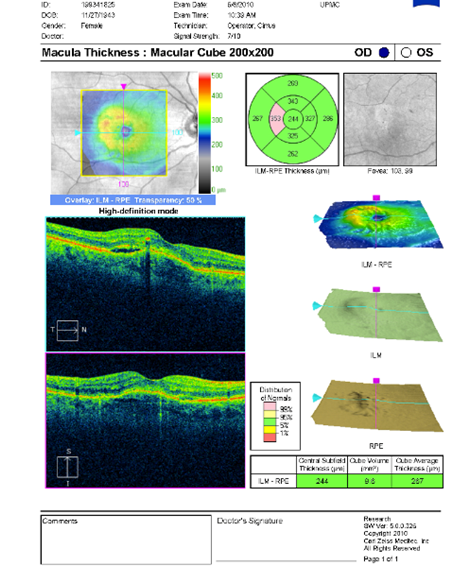

FUNDUS DESCRIPTION: |

OD OS |

OD Red-Free: Pre-Injection: Arterial: A-V: Venous: Recirculation: Late:

OS Red-Free: Venous: Recirc: Late:

Impression